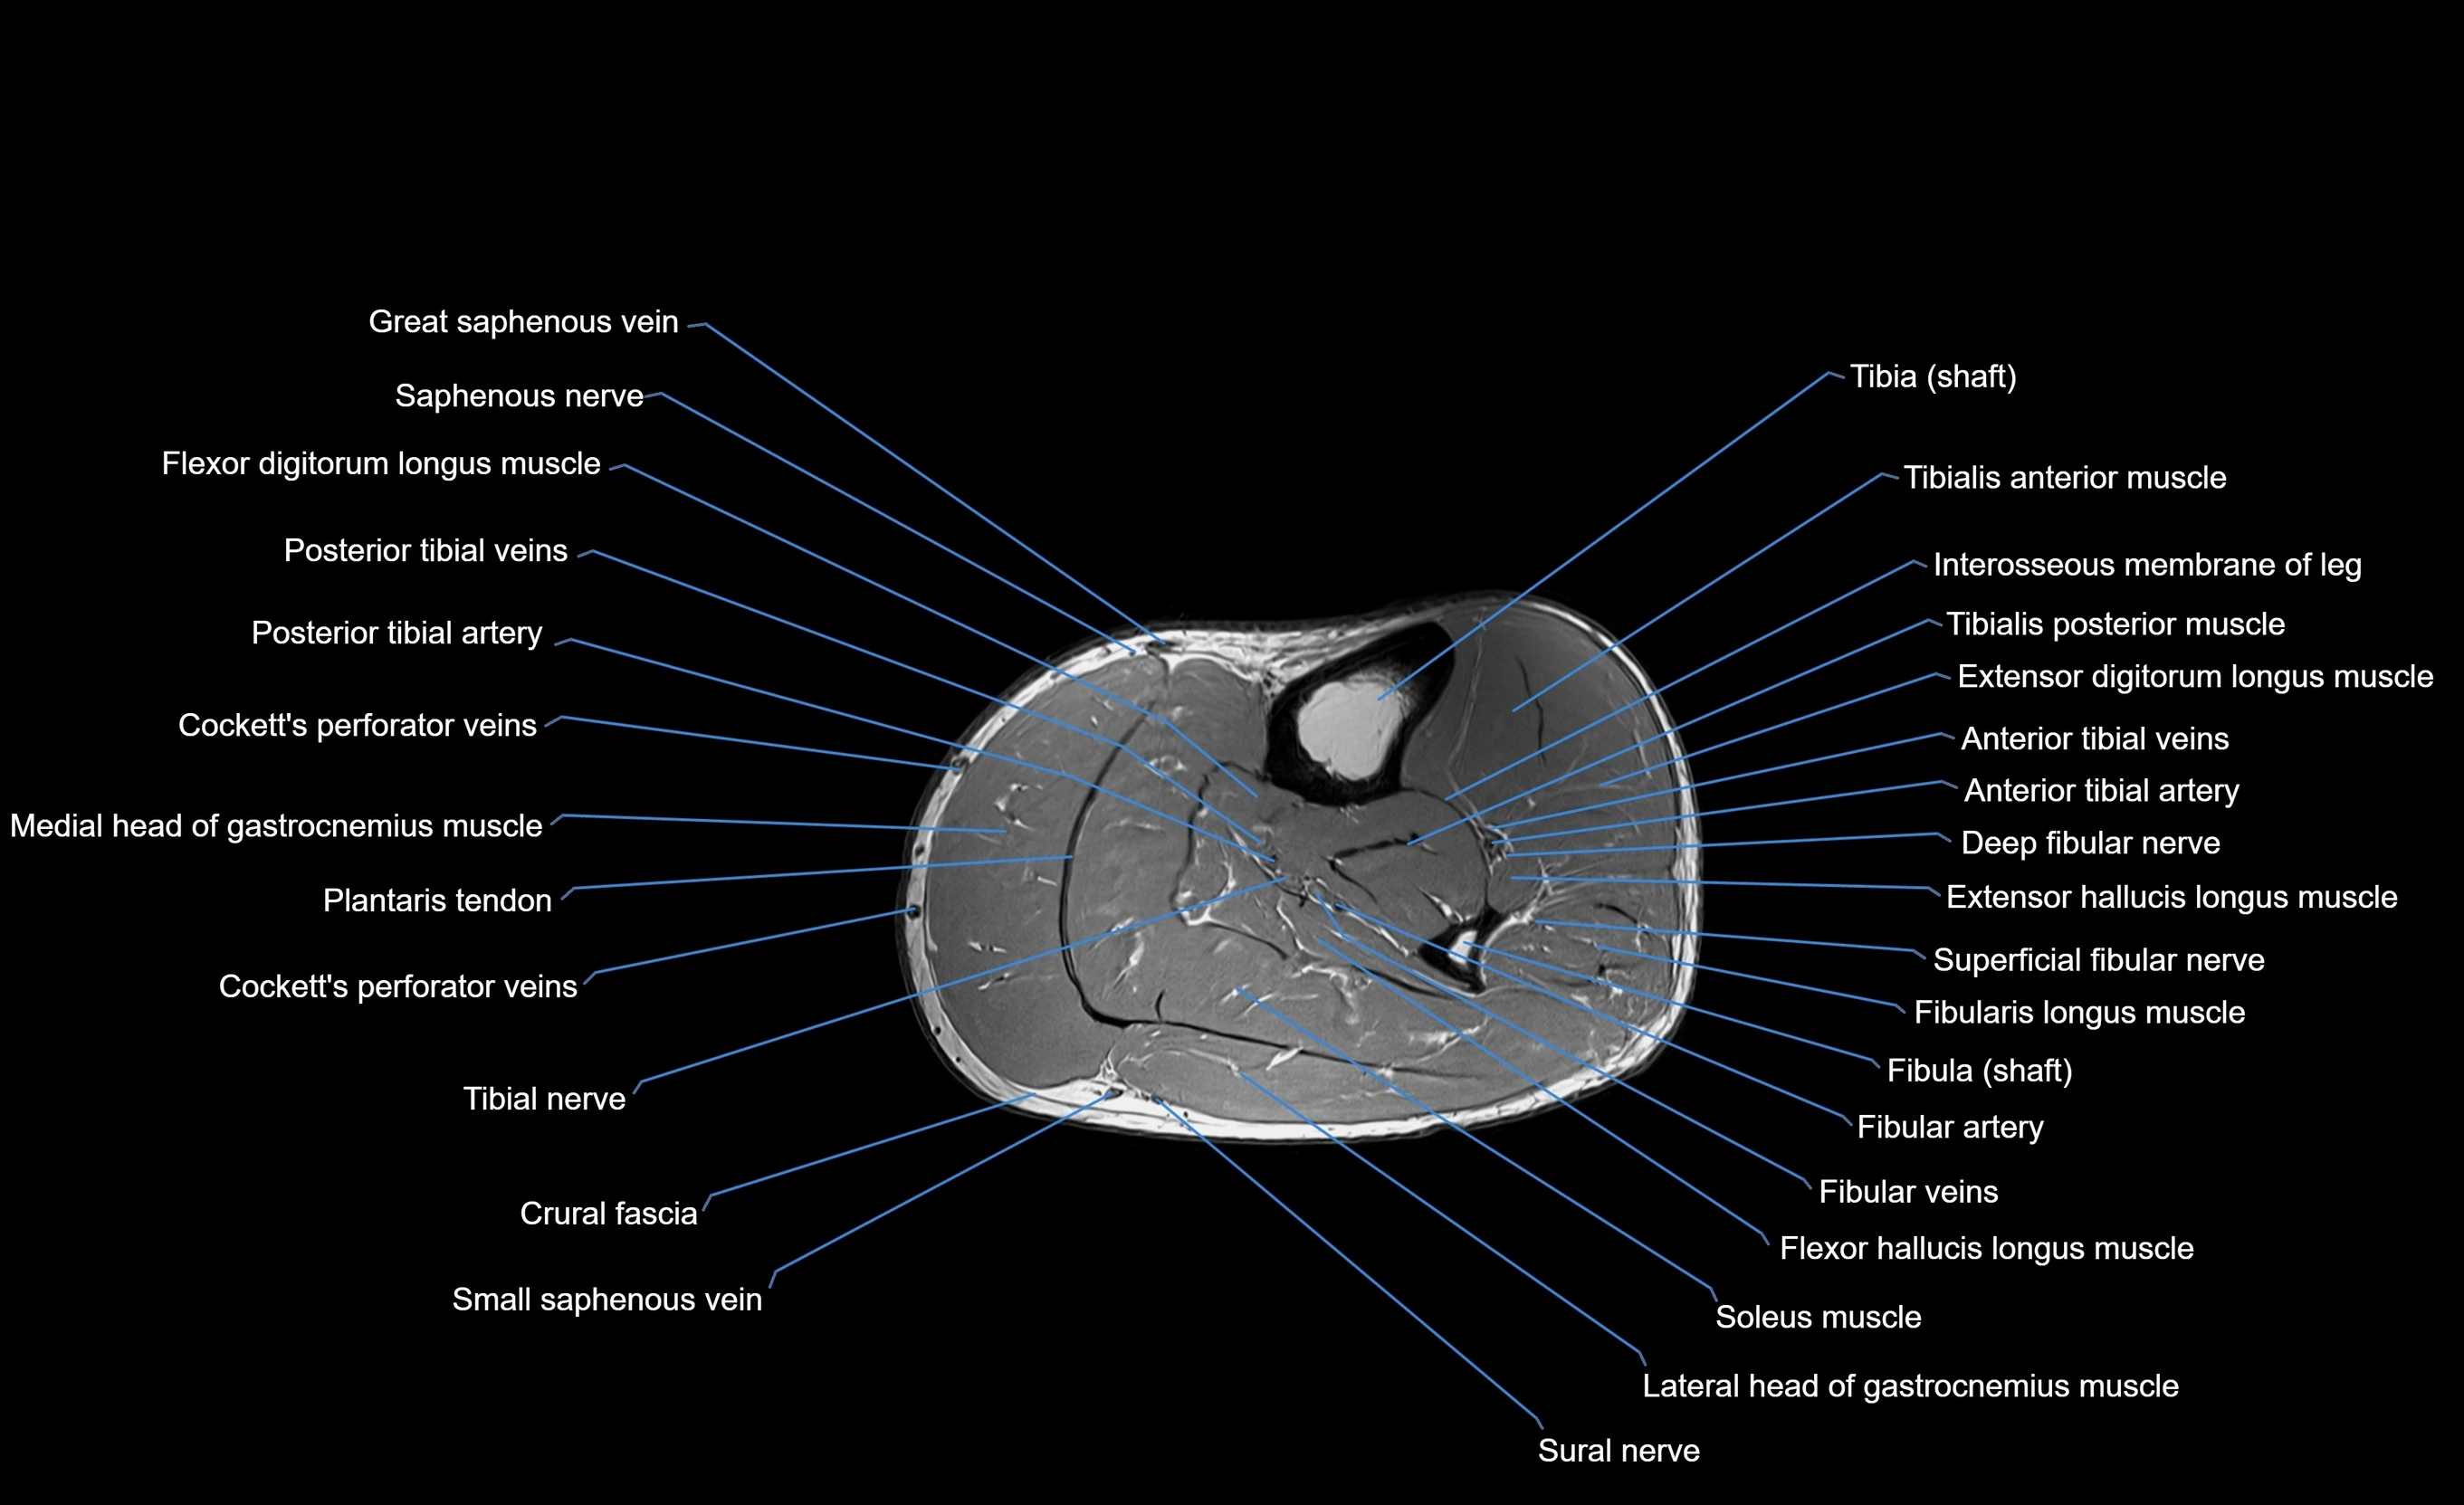

MRI image